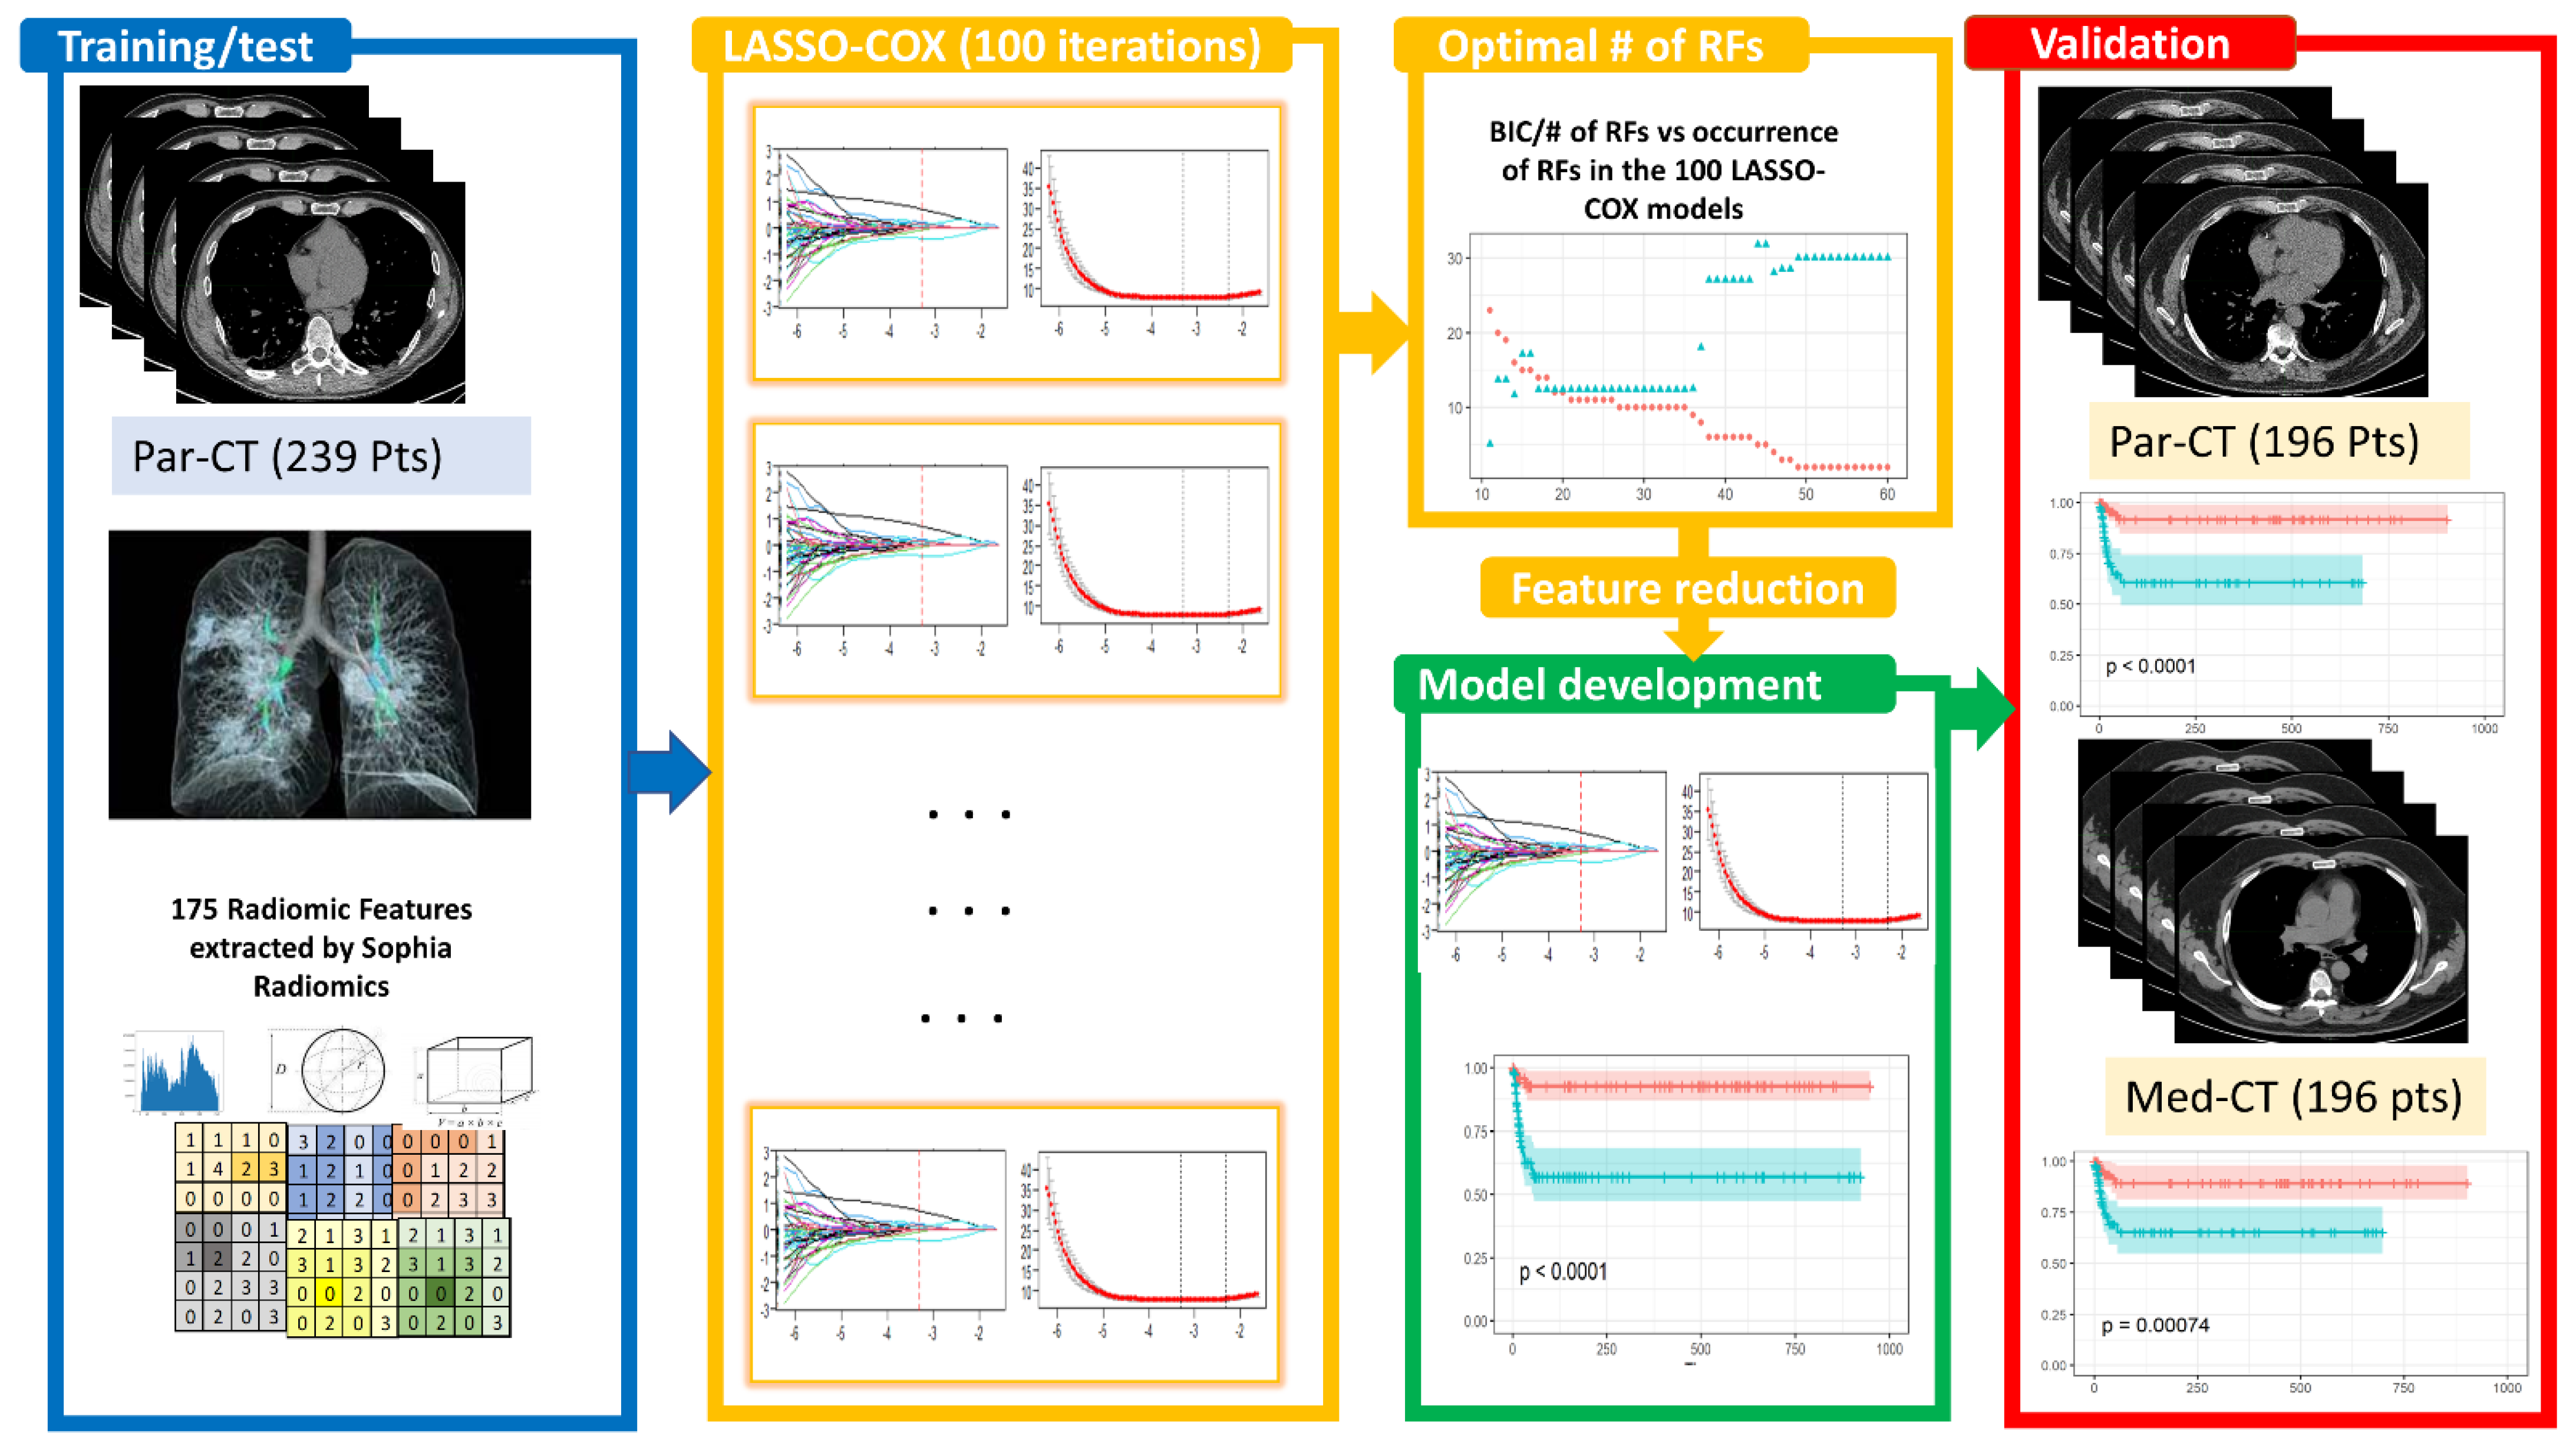

2.2. Image Segmentation and Feature Extraction

2.3. Predictive Model Building

2.3.1. Feature Selection

2.3.2. Bayesian Information Criterion (BIC)

2.3.4. Model Evaluation through Survival Curves

3.2. Image Reconstruction and VOI Delineation Results

3.3. LASSO-Cox for Feature Selection